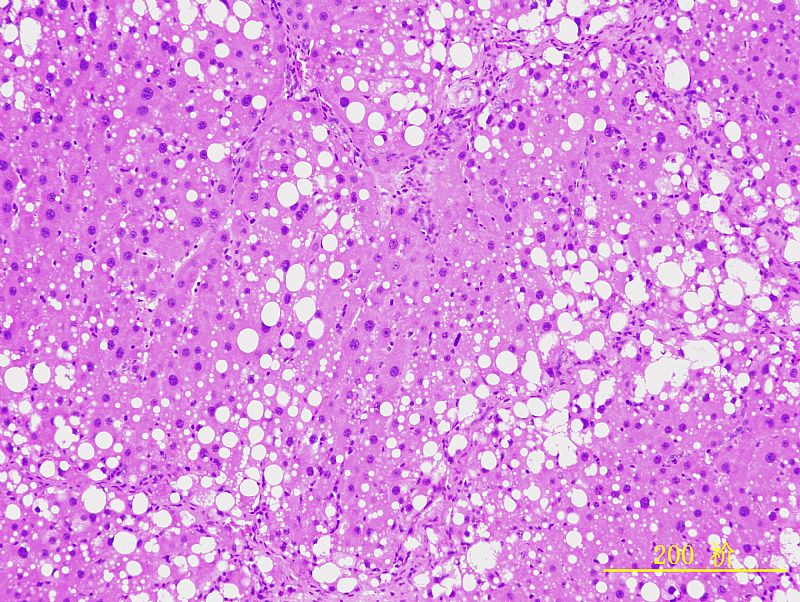

请教各位虫子,我做的是肝纤维模型,皮下注射CCl4 8周造模。每周两次,3ml/kg,40%CCl4。 因为对肝组织的组织形态没有深入的学习,对肝组织的具体病变描述无从入手,不知肝细胞脂肪病变、炎性浸润等是怎样的,附上几张实验图片(HE&Sirus red),请教各位行家,还望各位老师不吝赐教,一一指点下!谢谢大家,另外祝大家节日快乐呵呵 |